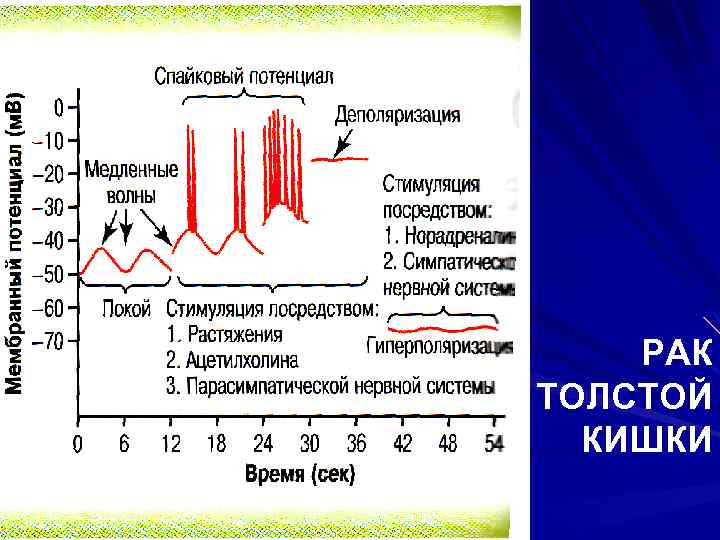

РИТМИЧЕСКАЯ АКТИВНОСТЬ МЕДЛЕННЫЕ ВОЛНЫ РАСПРОСТРАНЯЮЩИЙСЯ (СПАЙКОВЫЙ) ПОТЕНЦИАЛ

РИТМИЧЕСКАЯ АКТИВНОСТЬ МЕДЛЕННЫЕ ВОЛНЫ РАСПРОСТРАНЯЮЩИЙСЯ (СПАЙКОВЫЙ) ПОТЕНЦИАЛ

МЕДЛЕННЫЕ ВОЛНЫ ВОЛНООБРАЗНЫЕ ИЗМЕНЕНИЯ ПОТЕНЦИАЛА ПОКОЯ ГЛАДКИХ МЫШЦ (это не ПД!) h = 5 – 15 м. В, ν = 3 – 12 мин-1: Желудок = 3 Duodenum = 12 Ileum = 9 СОКРАЩЕНИЯ ВЫЗЫВАЮТ ТОЛЬКО В ЖЕЛУДКЕ

МЕДЛЕННЫЕ ВОЛНЫ ВОЛНООБРАЗНЫЕ ИЗМЕНЕНИЯ ПОТЕНЦИАЛА ПОКОЯ ГЛАДКИХ МЫШЦ (это не ПД!) h = 5 – 15 м. В, ν = 3 – 12 мин-1: Желудок = 3 Duodenum = 12 Ileum = 9 СОКРАЩЕНИЯ ВЫЗЫВАЮТ ТОЛЬКО В ЖЕЛУДКЕ

МЕДЛЕННЫЕ ВОЛНЫ КАК ПРАВИЛО, СОКРАЩЕНИЙ КИШКИ НЕ ВЫЗЫВАЮТ М. В. → СПАЙКОВЫЕ ПОТЕНЦИАЛЫ → СОКРАЩЕНИЯ ГЛАДКИХ МЫШЦ

МЕДЛЕННЫЕ ВОЛНЫ КАК ПРАВИЛО, СОКРАЩЕНИЙ КИШКИ НЕ ВЫЗЫВАЮТ М. В. → СПАЙКОВЫЕ ПОТЕНЦИАЛЫ → СОКРАЩЕНИЯ ГЛАДКИХ МЫШЦ

СПАЙКОВЫЕ ПОТЕНЦИАЛЫ ВОЗНИКАЮТ при -40 м. В ДЛЯТСЯ 10 – 20 мс, это ~ 25 раз дольше, чем ПД в нерве ПРИЧИНА: медленные Ca/Na-каналы

СПАЙКОВЫЕ ПОТЕНЦИАЛЫ ВОЗНИКАЮТ при -40 м. В ДЛЯТСЯ 10 – 20 мс, это ~ 25 раз дольше, чем ПД в нерве ПРИЧИНА: медленные Ca/Na-каналы

ДЕПОЛЯРИЗУЮТ МЕМБРАНУ РАСТЯЖЕНИЕ ACh PS Некоторые ЖК-гормоны

ДЕПОЛЯРИЗУЮТ МЕМБРАНУ РАСТЯЖЕНИЕ ACh PS Некоторые ЖК-гормоны